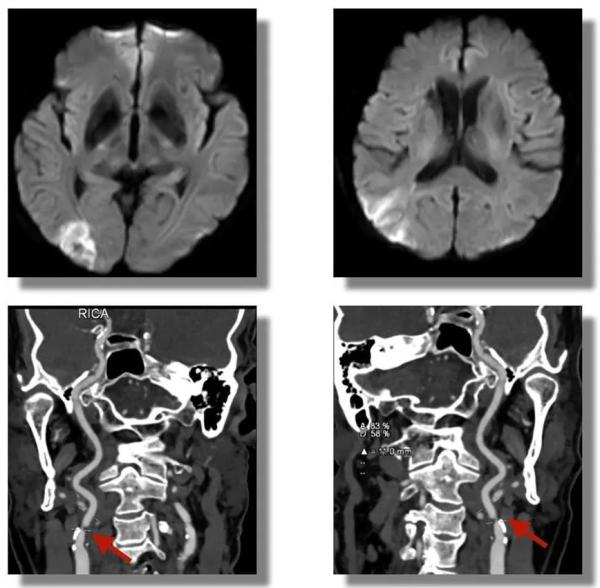

通过我院卒中绿色通道,该患者从到达急诊到应用溶栓药物(DNT)时间窗为28分钟。对于脑卒中患者来说,时间就是生命,“快”是救治的关键。随后,颅脑核磁共振证实,患者此次发生的是右侧大脑半球新发梗死灶,进一步的血管检查发现,患者右侧颈内动脉起始段重度狭窄。经过全脑血管造影术,进一步明确诊断,立即给予支架置入成形术。

红色箭头所指位置显示, 患者右侧颈内动脉起始段重度狭窄。